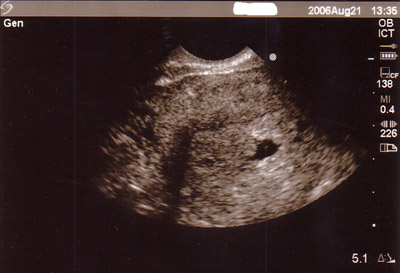

August 21, 2006: Three Days Later…

Today was a normal day, like any other. I went to work like usual and even went out to an early birthday lunch. I had been having a stressful morning with work and wasn’t feeling in high spirits. Friday’s appointment was still looming over me and the anxiety of Thursday’s ultrasound was weighing on me too. After lunch I went to the bathroom and noticed some significant brown spotting. I spotted last Friday and Saturday from the pap smear but enough time had passed that this was cause for alarm. I tried to go back to working but the tears came a rollin’ down my face and I told my manager I needed to speak with her. No one at work knew I was pregnant and I wasn’t going to share the joyous news until I had some resolution to last Friday’s ultrasound fiasco. But as I was clearly not in the mindframe

;to buckle down and get to work, I spilled it in a totally dramatic fashion. The conversation went something like this, “(WAHHHH) You don’t know this, but I’m pregnant (sniff sniff) and I had a bad appointment last Friday and now I’m spotting and there is something wrong!” I cried and called my doctor’s office where I talked to an awesome male nurse who told me I needed to be seen and that the OB Dept would be getting back to me. Whatever, getting back to me when? I promptly packed up my things and high-tailed it to the doctor’s office without and appointment where the poor check-in receptionist got an ear-full and a tear-full outta me. She promised to get me in to see my RNP in 15 minutes. God bless her. I was called in and when they went to take my blood pressure, more tears. Ugh! I was sent to an exam room and my RNP came in and I gave her my sob story. She took a looksy in my nether regions to look for any “material” in the vaginal canal. That was a nice way of saying “fetal material” I guess. Thank God she found nothing. She decided to try the vaginal ultrasound again but reminded me that it had only been 3 days since my last visit and because she didn’t find anything then, she may not find anything now. Again, she couldn’t find my mysterious uterus so she called in a female OB. This woman was neither nice, sympathetic, nor gentle. She was like, “Look, I see a dot, nothing really yet. You are not far enough along to see anything. The bleeding you had was implantation bleeding.” I’m like, “WHAT?” I told her, “No, not implantation bleeding. If I was having implantation bleeding I wouldn’t know I was pregnant yet and I’ve known I was pregnant since August 3rd. I had implantation bleeding on July 28th.” She barely listened and walked away. My RNP thought the bleeding was just aggravation from the pap smear and she ordered another blood test to check my pregnancy hormone level. I have to come back Wednesday afternoon and give another blood sample to test the level 48 hours later because the levels are supposed to be multiplying exponentially. She told me to keep my dating ultrasound appointment on Thursday and that she would call me with the results. I must admit, even just seeing the tiny dot, even without a heartbeat in my ultrasound picture gave me a great deal of comfort. To my surprise when I walked out of the appointment, [Big Daddy P] was standing there. He knew to come, even though all the voicemail said was, “P, I’m bleeding, something is wrong!” He just knew I was at the doctor’s office without an appointment. How wonderful to see him there, I got me a good man. Please send your prayers and good wishes. I could really use the comfort. Love, Lori & the Little One